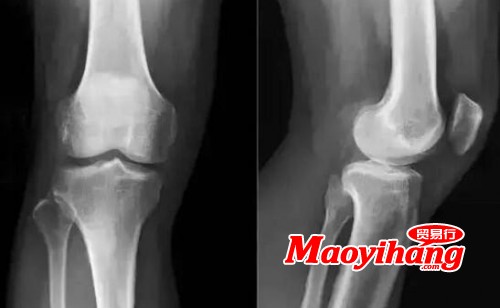

最近,發(fā)表在Science Translational Medicine期刊上,來(lái)自英國(guó)倫敦大學(xué)瑪麗女王學(xué)院的研究人員報(bào)道,一種新發(fā)現(xiàn)的分子可以誘導(dǎo)骨骼和軟骨在遭受缺損后的長(zhǎng)期再生以及癥狀緩解,因而可能在治療骨關(guān)節(jié)炎中發(fā)揮作用。

在這項(xiàng)新的研究中,這些研究人員研究了一種叫做agrin的分子,發(fā)現(xiàn)它可以通過(guò)招募和激活存在于關(guān)節(jié)中的成體干細(xì)胞來(lái)修復(fù)軟骨。

這個(gè)機(jī)制和身體在胚胎中第一次形成骨骼時(shí)使用的機(jī)制是一樣的。這項(xiàng)研究表明,激活這一機(jī)制可有效促進(jìn)正常情況下無(wú)法愈合的軟骨損傷的愈合方法。

在小鼠實(shí)驗(yàn)中,將含有聚集蛋白的凝膠(以下稱為含有聚集蛋白的凝膠)注射到關(guān)節(jié)表面缺損中。8周后發(fā)現(xiàn)能誘導(dǎo)骨和軟骨的長(zhǎng)期再生,比注射無(wú)聚集素凝膠的對(duì)照組效果多。

6個(gè)月后,與對(duì)照組相比,注射聚集蛋白的凝膠的綿羊軟骨和骨的修復(fù)也有所改善。在整個(gè)研究過(guò)程中,這些綿羊也花了更多的時(shí)間玩耍,減少了休息時(shí)間,這表明這種改善的修復(fù)與功能的改善有關(guān)